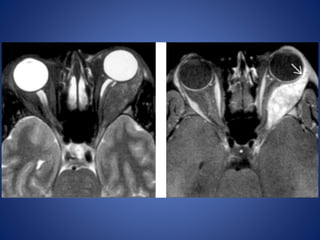

Imaging : MRI is the modality of choice with hyper intense signal of

T2WI due to fluid and edema. Fat Sat contrast enhanced T1WI will show

areas of demyelination. CT relatively insensitive.

Straightening and thickening

of right optic nerve.

Optic Neuritis. CE Fat Sat T1W axial (B) MR images demonstrate subtle

enlargement and enhancement of the left optic nerve (curved arrow).

T2WI (C) demonstrates corresponding increased signal intensity (straight

arrow).

OPTIC NEURITIS Acute inflammationof optic nerve , commonly associated with multiple sclerosis. Edema and inflammatory cells infiltrate the nerve resulting in uniform swelling and focal demyelination. Imaging : MRI is the modality of choice with hyper intense signal of T2WI due to fluid and edema. Fat Sat contrast enhanced T1WI will show areas of demyelination. CT relatively insensitive. Straightening and thickening of right optic nerve.

Optic Neuritis. CEFat Sat T1W axial (B) MR images demonstrate subtle enlargement and enhancement of the left optic nerve (curved arrow). T2WI (C) demonstrates corresponding increased signal intensity (straight arrow).